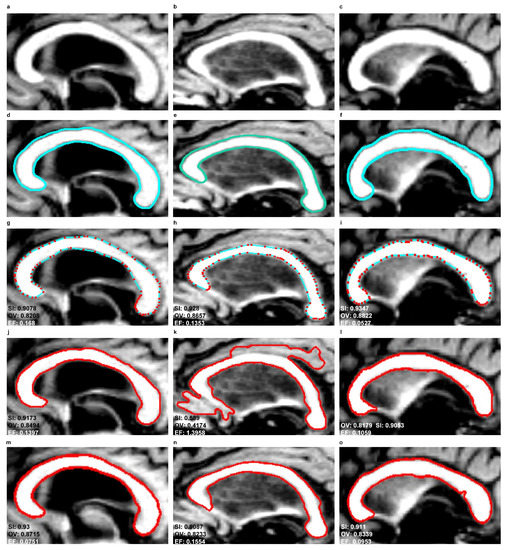

Figure 10 and Figure 11 show the segmentation results produced by the EM, SBGFRLS and DRLSE models as well as the contours manually traced by an experienced physician ( E 1 ). In the EM model, the CC contours obtained in the previous or subsequent slices of MR images can be used for initiations in the next or previous slices.

Figure 12 and Figure 13 demonstrate examples of 3D CC models produced using the segmentations obtained. The wrong segmentation in the plane makes the 3D models wrong as well. This is illustrated by examples from Figure 12h–l and Figure 13h–l.

As a result of the experiments carried out, the EM model produced significantly better results of the mean SI (92%) and OV (85%) indices than SBGFRLS (SI = 82%, OV =72%) and DRLSE (SI = 73%, OV = 67%). Segmenting the CC using the DRLSE model may produce the greatest underestimation, as proven by the lowest minimum values of the S I and O V indices, which, for the DRLSE, amount to 41% and 28%, as also shown in examples from Figure 11m,o. The DRLSE and SBGFRLS models allow high segmentation results to be obtained for single CC slices, which has also been demonstrated in source articles [13,14]. However, if the entire set of CC slices is analysed as necessary to obtain an accurate 3D CC reconstruction, wrong segmentations (under- or over-segmentations) are produced for some images.

The average mean value of the E F indice is the lowest for the DRLSE model and amounts to 9%. The EM and SBGFRLS models produced mean values of the EF indice amounting to 12% and 36% respectively, so if the SBGFRLS model is used, a very high over-segmentationmay occur.

Figure 10. Comparison of corpus callosum segmentation results for example MR images taken from three sets from the MIRIAD database. First column: ‘miriad_189_AD_M_05_MR_1’, second column: ‘miriad_190_AD_M_02_MR_1’, third column: ‘miriad_205_AD_F_05_MR_1’. First row: ROIs from MR images of the corpus callosum based on the sagittal plane, Second row: contours traced by a physician ( E 1 ), Third row: contours produced by the EM model, Fourth row: use of the SBGFRLS model, Fifth row: the DRLSE model.

Symmetry 10 00589 g010

Figure 11. Comparison of corpus callosum segmentation results for example MR images taken from three sets from the MIRIAD database. First column: ‘miriad_234_AD_M_03_MR_2’, second column: ‘miriad_244_AD_F_01_MR_2’, third column: ‘miriad_257_AD_F_05_MR_1’. First row: ROIs from MR images of the corpus callosum based on the sagittal plane, Second row: contours traced by a physician ( E 1 ), Third row: contours produced by the EM model, Fourth row: use of the SBGFRLS model, Fifth row: the DRLSE model.

Symmetry 10 00589 g011